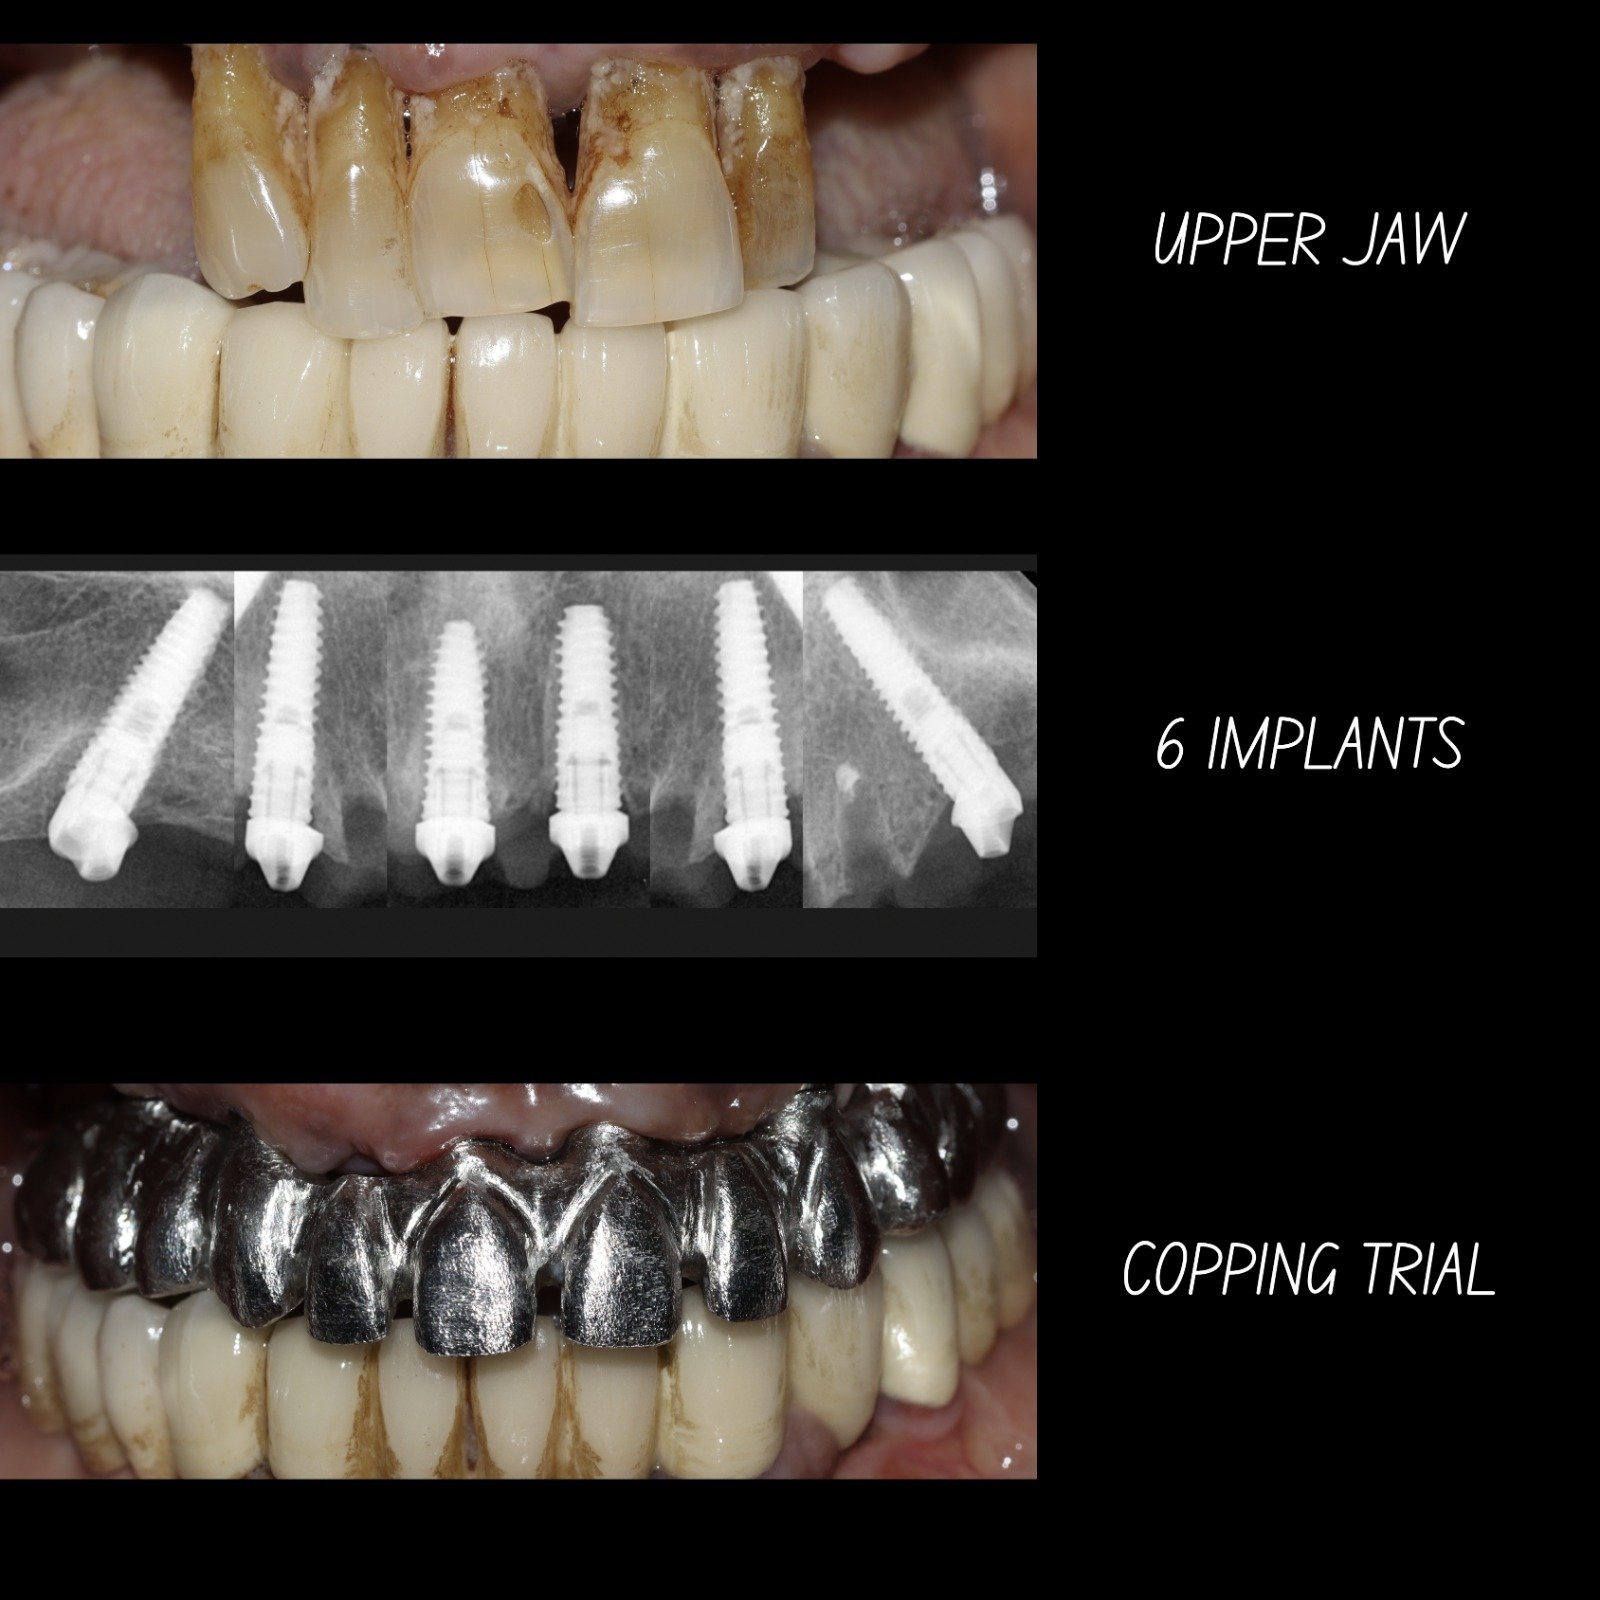

Our clinic uses advanced digital implant dentistry, guided by one of Pune's top expert dentists, including CBCT 3D scans, intraoral scanners, and precision-guided planning to ensure accurate implant placement, faster healing, and predictable results.

| All-on-4 (per arch) | ₹1,50,000 – ₹3,50,000 |

| All-on-6 (per arch) | ₹2,00,000 – ₹4,50,000 |